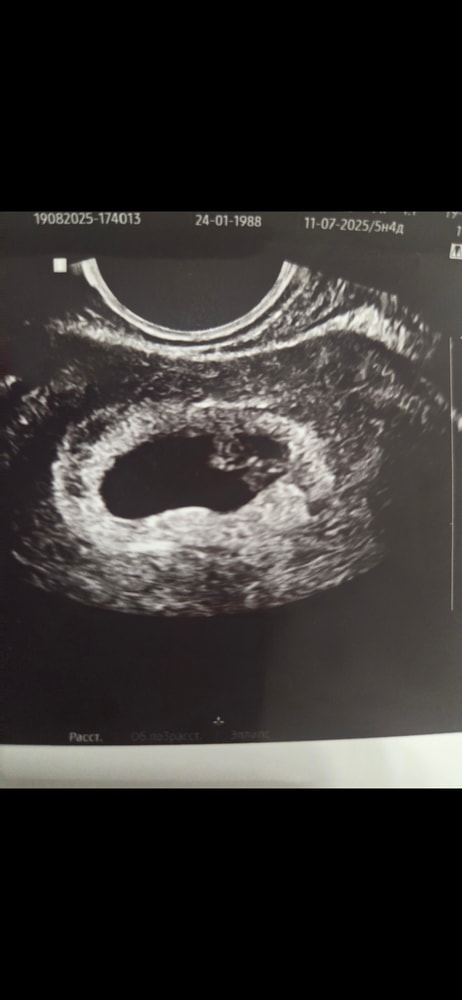

Вера , вот здесь первое узи, когда их увидели. Акушерский 5,4 недели Изображение